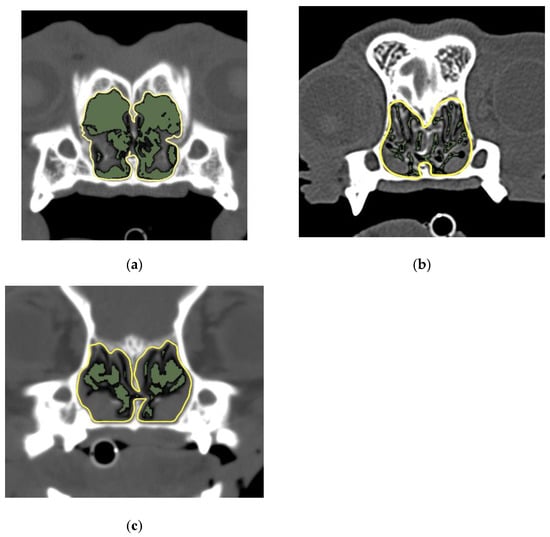

2.3.1. 2D Region Growing

2.3.2. Measurement of the AA/NC Ratio